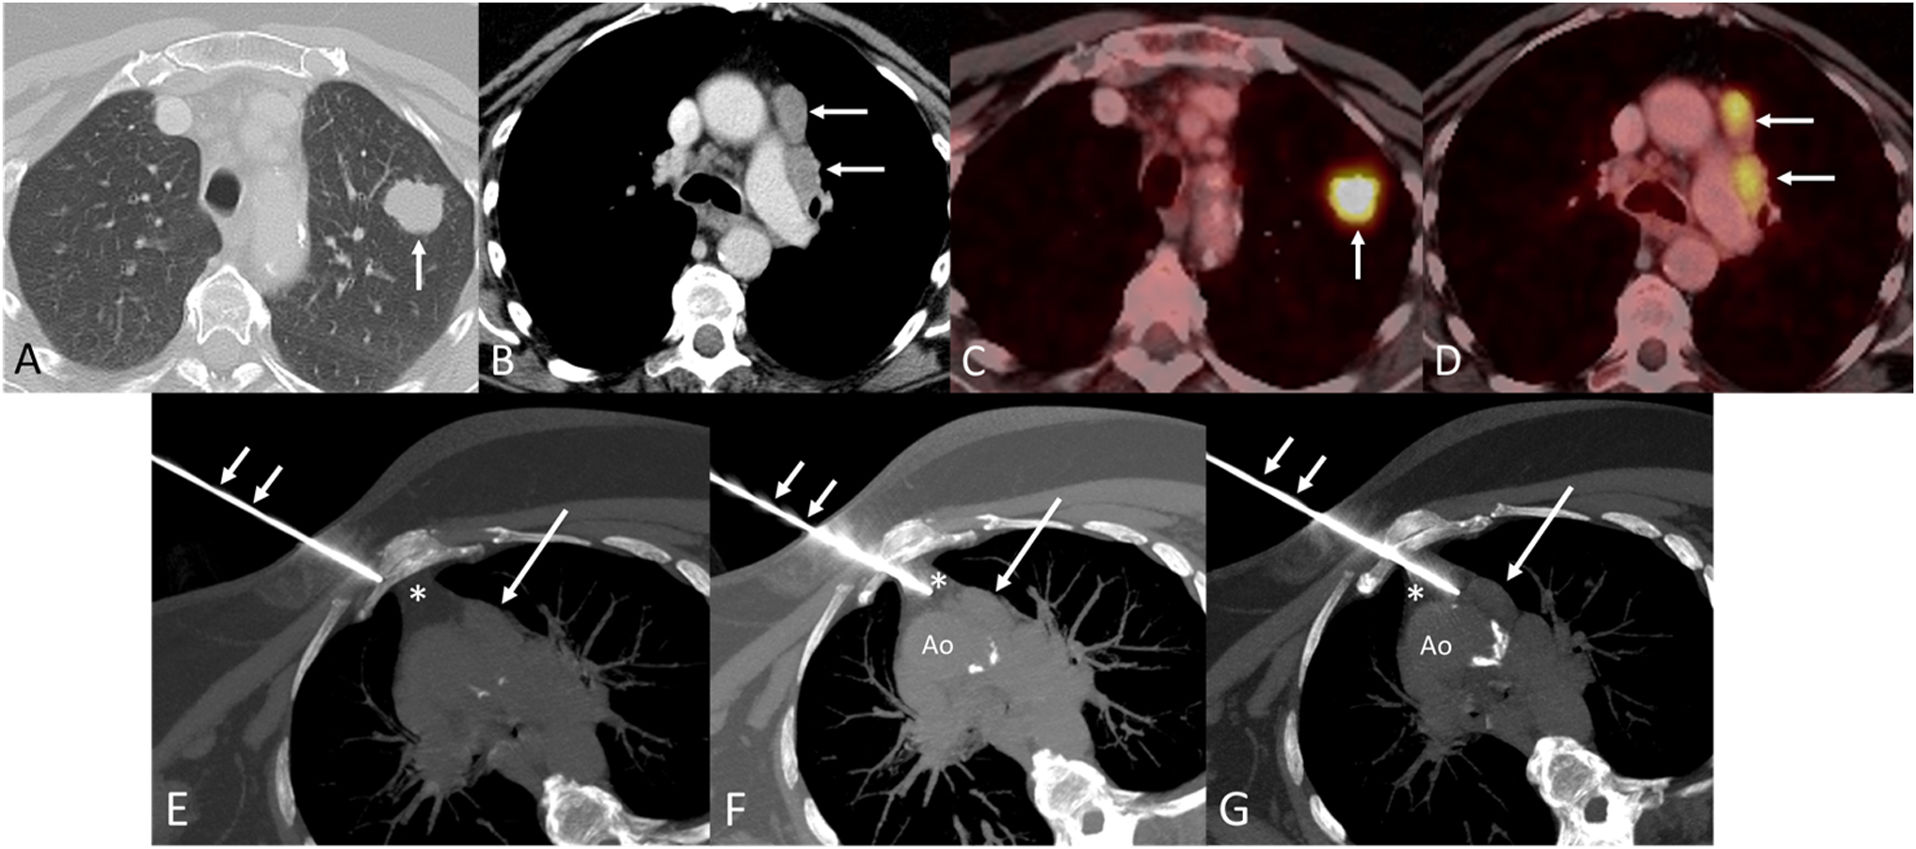

A 67-year-old patient with a history of smoking was found to have a solid nodule in the left upper lobe (LUL) and enlarged ipsilateral mediastinal lymph nodes involving stations 3A and 6, with extension to station 5, on chest computed tomography (CT) (Fig. 1A and B). Whole-body positron emission tomography–computed tomography (PET/CT) demonstrated intense fluorodeoxyglucose (FDG) uptake in both the LUL nodule and the ipsilateral enlarged mediastinal lymph nodes (Fig. 1C and D), consistent with clinical stage cT1cN2bM0 disease.

(A) Axial chest CT image (lung window) showing a solid nodule in the left upper lobe (arrow). (B) Axial CT image (mediastinal window) demonstrating enlarged lymph nodes in the prevascular and paraaortic stations of the ipsilateral mediastinum (arrows). (C and D) Axial fused PET/CT images showing intense FDG uptake in the left upper lobe nodule (C) and the ipsilateral mediastinal lymph nodes (D) (arrows). (E–G) Axial CT images demonstrating progressive transmediastinal needle insertion (short arrows) through the chest wall (E) and mediastinal fat pad (F) to reach the enlarged preaortic lymph node (large arrow, G). The asterisk denotes the transmediastinal trajectory. Note the right parasternal extrapulmonary approach and semilateral decubitus patient positioning to avoid aortic (Ao) puncture.

Because the involved mediastinal lymph node stations were not accessible using endobronchial ultrasound (EBUS), a percutaneous CT-guided transmediastinal biopsy was performed via a parasternal approach (Fig. 1E–G). The procedure was uneventful and confirmed metastatic involvement of the paraaortic lymph nodes, allowing comprehensive immunohistochemical and molecular characterization. The patient subsequently underwent definitive chemoradiation followed by consolidation immunotherapy.